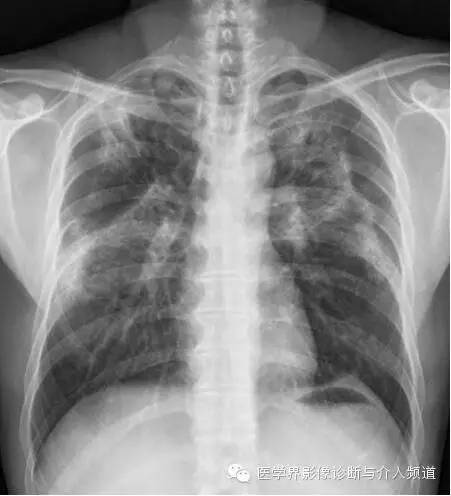

初始胸片

初始胸片示两肺野多灶性斑片影,其中两肺上野靠近外周可见边界欠清的实变影,这是典型的慢性嗜酸性粒细胞性肺炎“肺水肿反转影”的表现。CT示两肺叶多灶性非节段性实变影,病变以两上肺周围性分布为主。

CEP的典型影像学表现:普通X线平片为非节段性、分布广泛互相融合的肺泡及间质性实变,病变以中上肺周围性分布为主,表现为“肺水肿反转影”。CT或HRCT表现为一侧或两侧融合性实变、斑片状实变、磨玻璃影、条带状致密影,实变灶与正常肺组织的分界截然清楚。此种典型征象并非见于所有CEP病例。